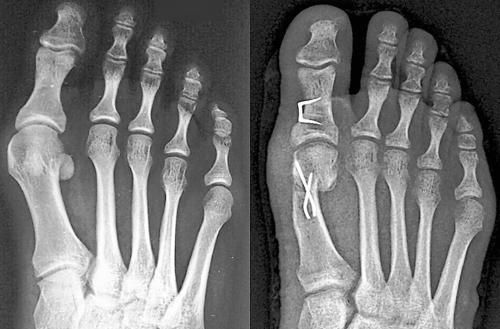

In den meisten Fällen werden Sehnen und Gelenkkapsel korrigiert, um die Fehlstellung des großen Zehs zu verringern. Der erste Mittelfußknochen und oft auch das Grundglied der Großzehe werden durchtrennt und so verschoben, dass der Zeh wieder geradesteht. Manchmal muss das erste Mittelfußgelenk auch versteift werden. Dabei kommen Metallplatten, Schrauben und Drähte zum Einsatz. In den ersten Wochen nach der Operation muss der Fuß stabil gehalten werden.